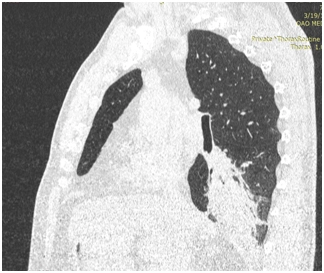

Фиброателектаз S5: объяснение и примеры на изображениях